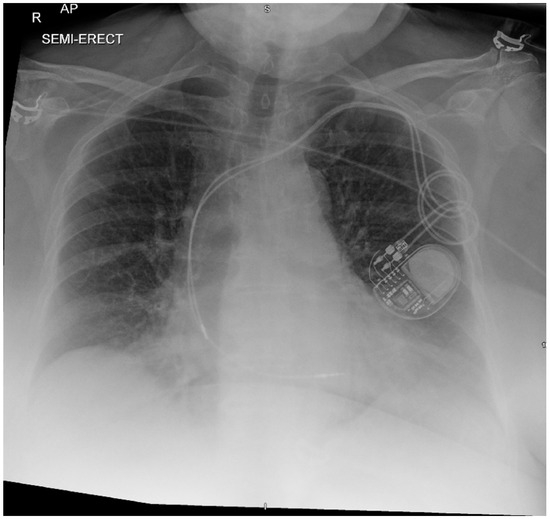

Background/Objectives: Twiddler’s syndrome is an uncommon but clinically important complication of implantable cardiac devices, in which generator rotation within the pocket results in lead torsion, lead retraction, and device malfunction. Recurrence can necessitate repeated surgical intervention and may be preventable through early risk

Background/Objectives: Twiddler’s syndrome is an uncommon but clinically important complication of implantable cardiac devices, in which generator rotation within the pocket results in lead torsion, lead retraction, and device malfunction. Recurrence can necessitate repeated surgical intervention and may be preventable through early risk identification and procedural strategies. Methods: We describe a single-centre case series of three female patients with pacemaker-associated Twiddler’s syndrome. Clinical presentation, timing of lead retraction, management strategies (including pocket location and fixation approach), recurrence, and follow-up outcomes were reviewed. Results: All patients were older women and developed symptomatic device failure early after implantation, with radiographic confirmation of lead retraction and coiling occurring within three weeks in all cases. Recurrence was observed when enhanced preventive measures were not employed. Notably, in one patient, recurrence occurred after an initial revision in a second prepectoral pocket, prompting subsequent reimplantation in a subpectoral location with reinforced fixation and structured patient and family counselling, after which no further recurrence occurred at one year. In the remaining cases, revision with reinforced generator fixation and counselling was associated with stable lead position and satisfactory device function during follow-up. Conclusions: Twiddler’s syndrome most commonly presents in the first weeks following implantation. Proactive identification of at-risk patients and consideration of reinforced fixation and pocket strategies at the index procedure may reduce recurrence and avoid repeat interventions.

Figure 1